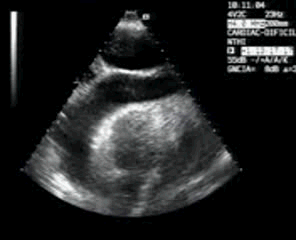

139. Ecocardiografía. Estudio Paraesternal Eje Largo.